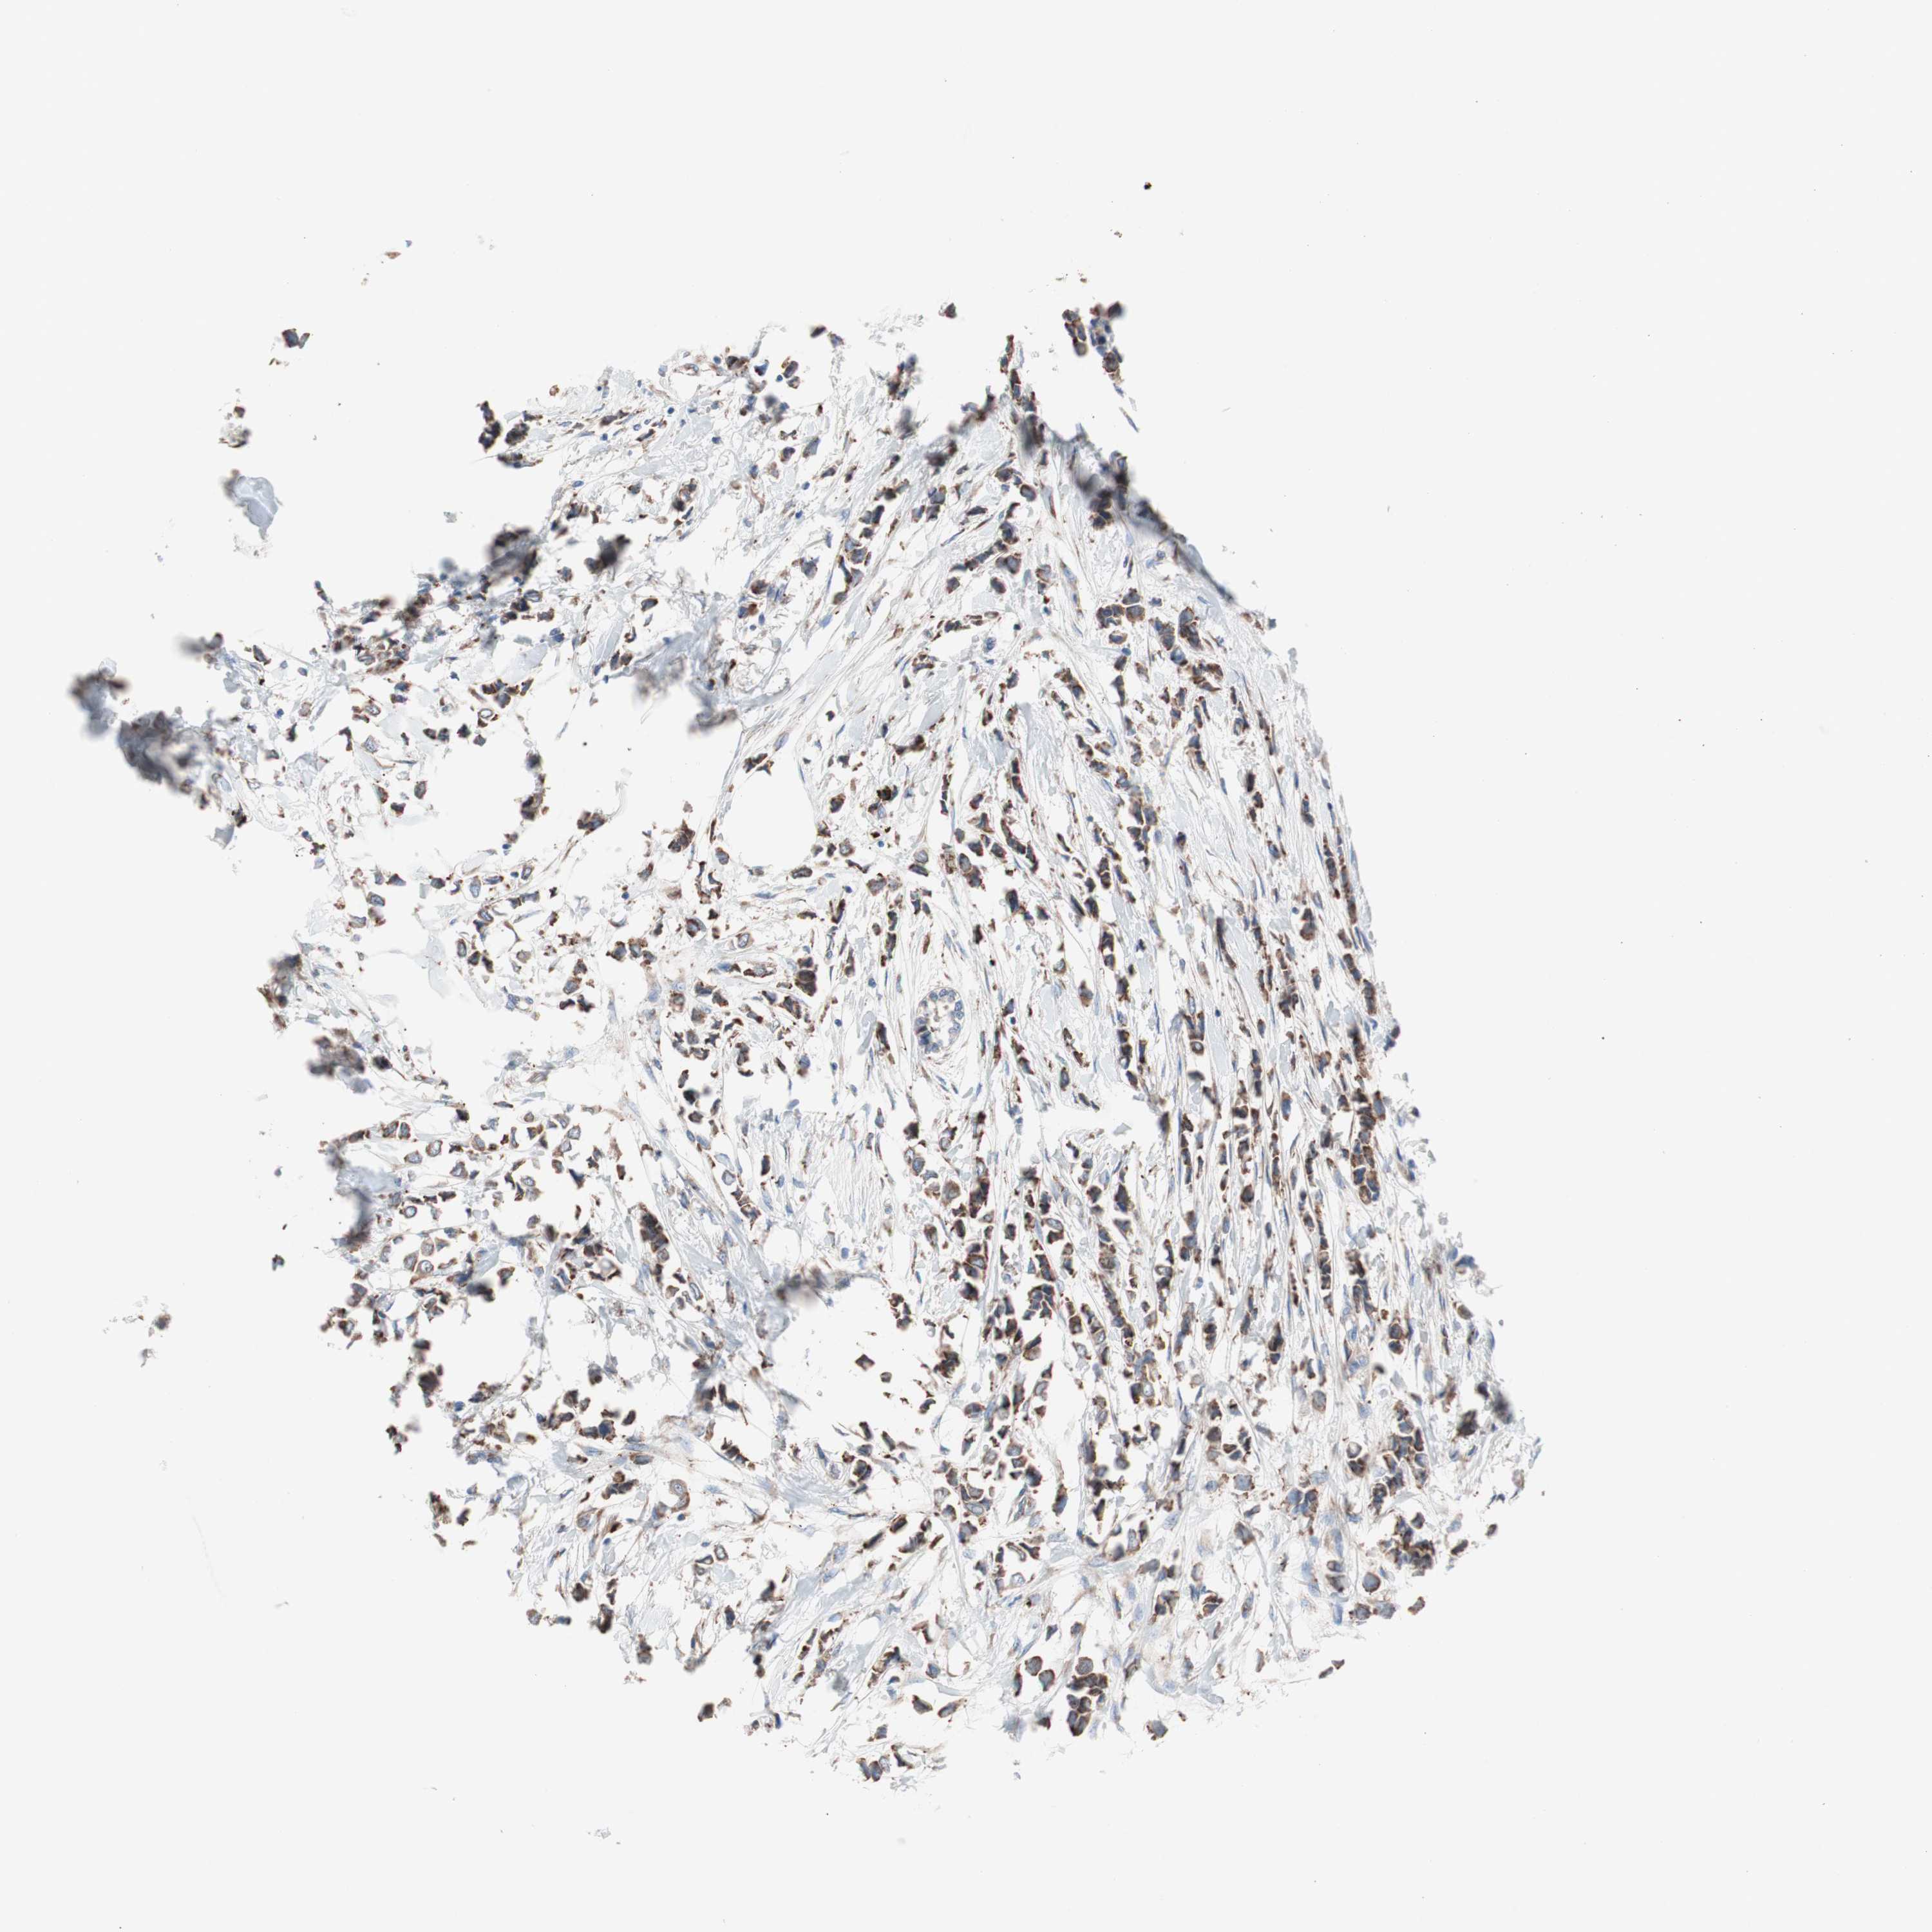

CANCER BREAST CANCER Show tissue menu

BRCA TCGA BRCA VALIDATION PROTEIN EXPRESSION